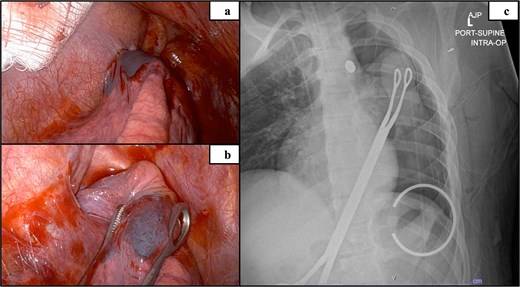

Trauma workup imaging began with a chest X-ray (CXR), triggering a chest CT given the bullet’s location in the mediastinum. With the bullet near the great vessels, a transthoracic echocardiography (TTE) and a CT using a cardiac gated/dissection protocol were obtained. The visualization of vasculature and normal anatomy was limited by metallic artifact from the foreign body (Fig. 1). The chest CT demonstrated the largest bullet fragment located in the region of the aortopulmonary window, with no measurable distance between the bullet fragment and inferomedial margin of the aortic arch (Fig. 2). Less than 2 mm of separation was visualized between the bullet and the superior aspect of the left main pulmonary artery (Fig. 2). There was no contrast extravasation from the vasculature to suggest active bleeding, and there was no obvious mediastinal fluid collection / hematoma. TTE also visualized the aortic arch and showed no clear injury with laminar flow across the aorta. His initial CXR demonstrated a normal cardio-mediastinal silhouette (Fig. 1a). A small pneumothorax was seen with 2 mm pleural separation but repeat CXR did not indicate expansion, so chest tube placement was deferred (Fig. 1a and b). Upper extremity imaging suggested soft tissue laceration and bullet trajectory without arterial damage.

Preoperative imaging indicating the location of the projectile and image obstruction by metal artifact: Initial CXR (a), day 2 CXR (b).